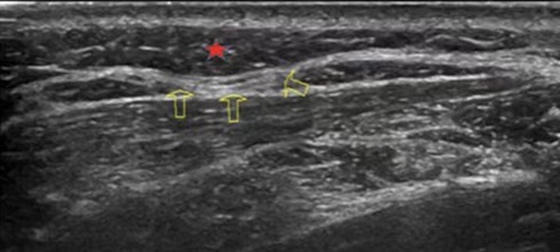

这是一位颈椎病患者肩背部超声下的影像,图像显示浅筋膜层局部增厚(星号),回声减低,左侧斜方肌肌外膜增厚,较模糊,局部呈层状且内凹,致斜方肌局部受压(箭头)。